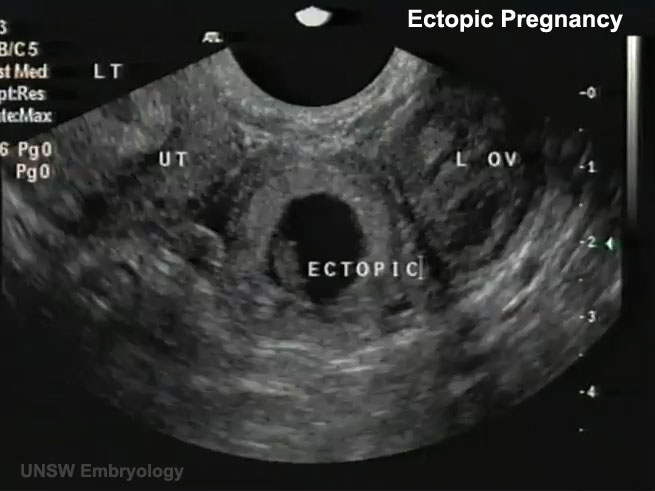

Ultrazvuk u ginekologiji (TAUS/TVUS) + Doppler

- Transabdominalni (TAUS) i transvaginalni (TVUS) ultrazvuk

- Procjena materice, endometrija, jajnika i male karlice

- Otkrivanje mioma, polipa, hiperplazije endometrija, cista i policističnih jajnika

- Dijagnostika i terapija endometrioze, cista, ektopične trudnoće i infertiliteta